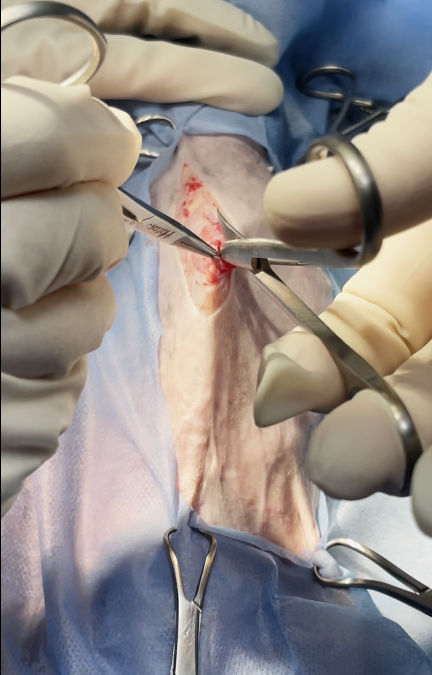

Surgical excision or partial hepatectomy is the treatment of choice.

in this case only biopsy sampling was obtained due to these reasons

owner was informed intraoperatively with :

lesion was close to major hepatic vessels & bile ducts, the risk of intraoperative bleeding or biliary leakage would be high, discouraging full lobectomy.

non-invasive, benign nature: conservative management was chosen instead of aggressive surgery

The cat’s advanced age (14 years) and possible comorbidities increased anesthesia and surgical risks

owners declined extensive surgery for risk reasons, opting for palliative management